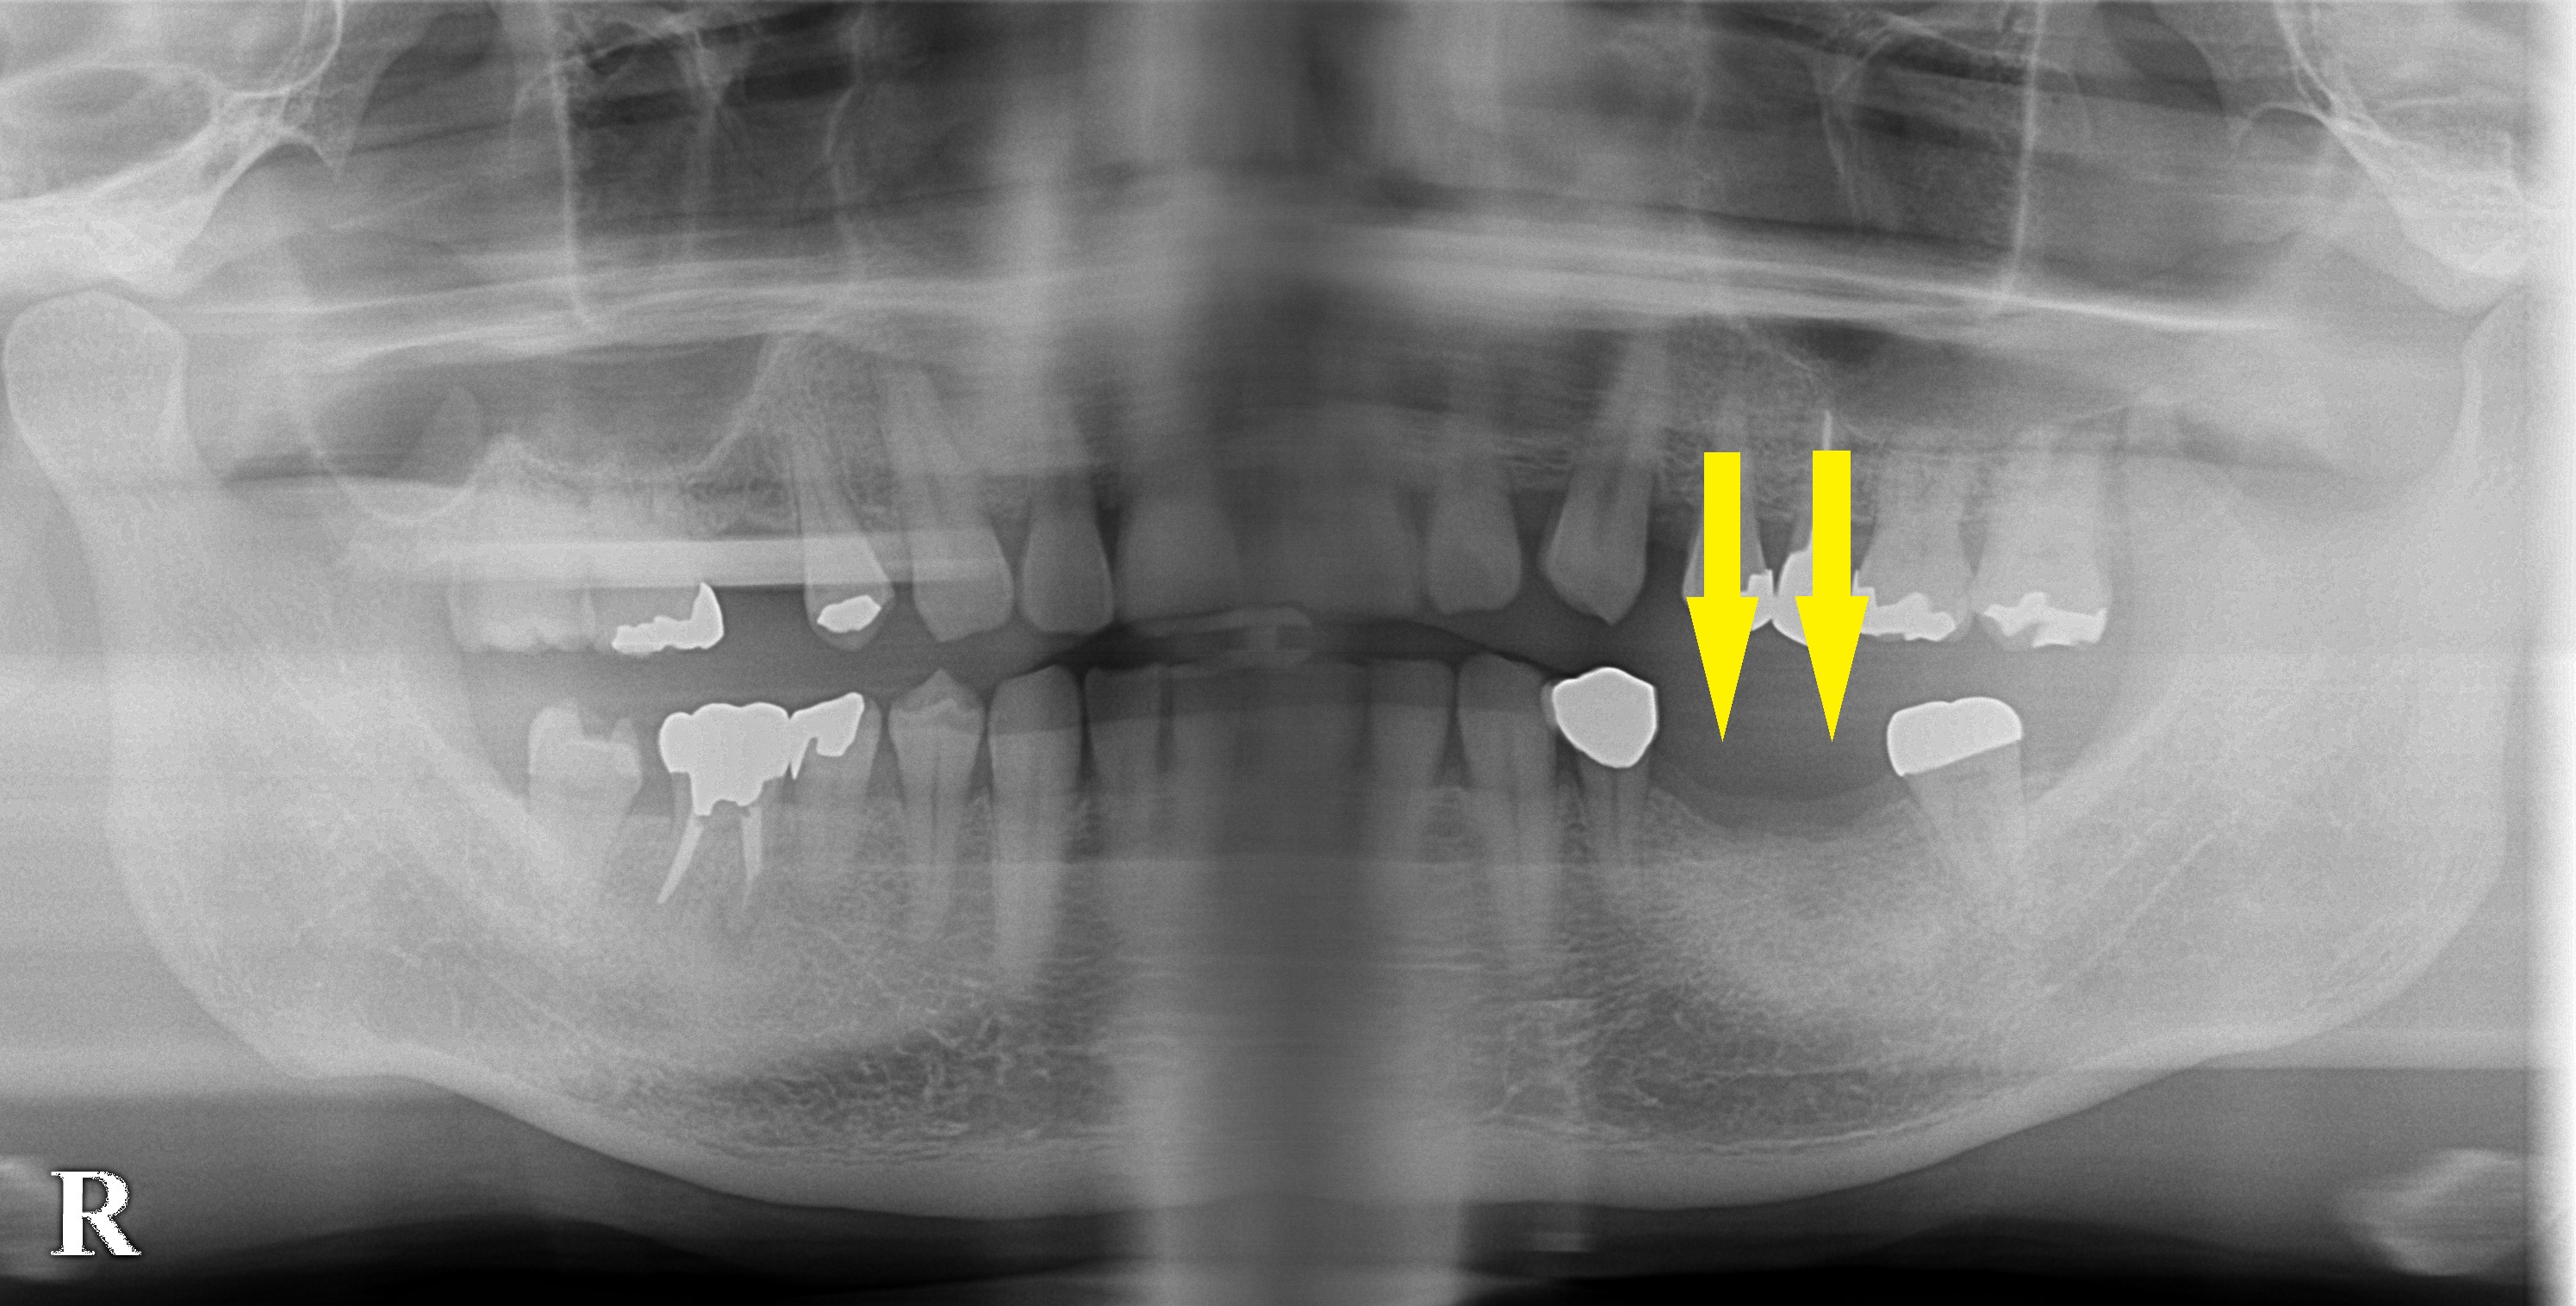

ダメになったブリッジのあとはインプラントで 今週のインプラント症例 2022.02.042026.01.19 患者様は名古屋在住の40代男性。 右下顎にブリッジが装着されていたのですが、1年ほど前に支えになっていた歯が脱落、しばらくそのまま過ごされていたそうです。 やはり奥歯で咬みにくいということで、インプラント治療を希望されて来院されました。 CTにて骨の量は十分で問題ありませんでしたので、 本日2本のインプラント埋入術を行いました。 症例・コラム一覧に戻る